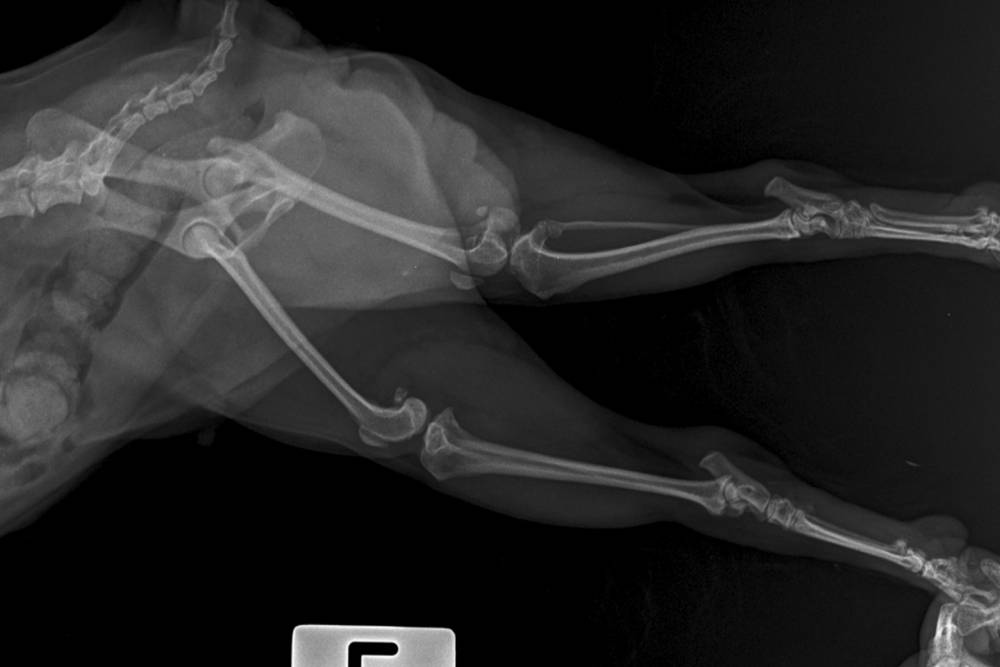

Two of the most common ones are femoral head ostectomy (FHO) and total hip replacement (THR). They work in completely different ways, and each is suited to different kinds of pets. Both can dramatically improve comfort and function when the right procedure is matched to the right patient.

FHO: Creating a Functional New Joint

What It Actually Does

Femoral head ostectomy sounds more intense than it is to explain. The surgeon removes the ball portion of the hip joint entirely. There is no replacement implanted. Instead, the body forms scar tissue over the following weeks that creates a “false joint” between the thighbone and the pelvis. That scar tissue cushion is what allows your pet to move comfortably again.

Total Hip Replacement: Restoring a Normal Hip

Total hip replacement works the same way it does in people. The surgeon replaces the damaged ball with a prosthetic ball on a stem that goes into the thighbone, and replaces the worn-out socket with a prosthetic cup. The new components are designed to recreate the mechanics of a normal, healthy hip joint.

- A thorough orthopedic exam

- Good-quality radiographs to see exactly what is going on